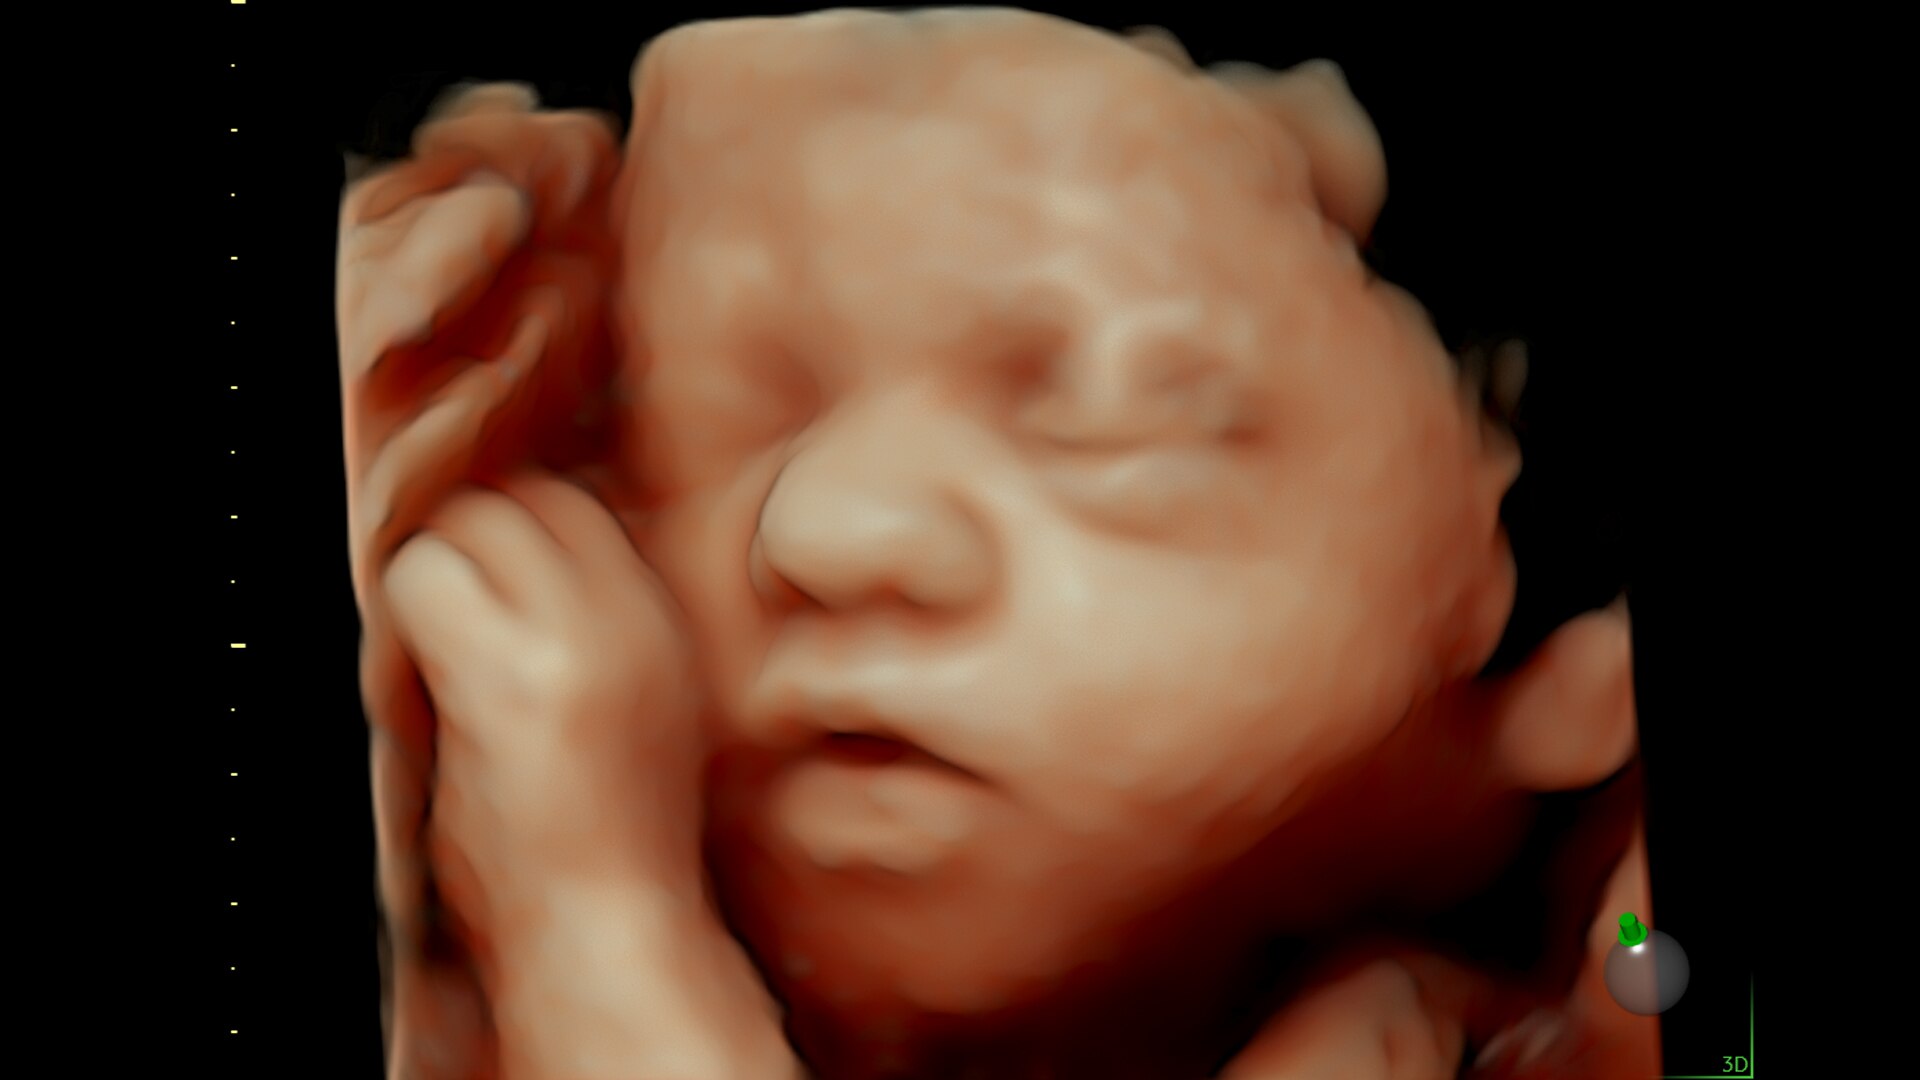

SonoLyst

SonoLyst* reduces the time to complete the standard ISUOG 2nd trimester exam requirements by 40%. And with SonoLyst live, it means no more stopping to freeze, annotate, or store.